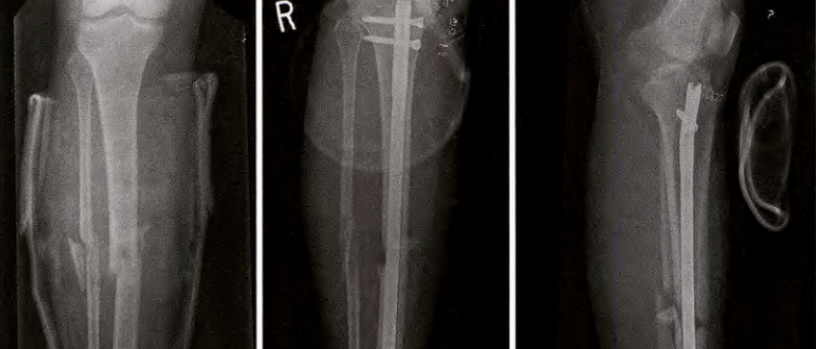

长骨偏心性膨胀性病变一般包括以下几个病变: 1、骨巨细胞瘤 2、动脉瘤样骨囊肿 3、成软骨细胞瘤 4、软骨黏液样纤维瘤 5、非骨化性纤维瘤 6、成骨细胞瘤 7、血管瘤 8、韧带样纤维瘤 9、甲状旁腺功能亢进之棕色瘤 10、良性纤维组织细胞瘤